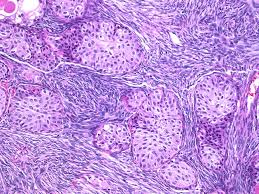

Brenner tumor

Prolif that comes from surface epithelium (like Walthards nests), usually b9

Gross: uniform, hard white nodule

Micro: solid nests of urothelioid-cells (sharply outlined c pale cytoplasm, nucleoli, groovy nucleus) surrounded by fibrous tissue

- can be malig (or borderline)

-- if cannot see b9 Brenner component can look like transitional cell carcinoma

IHC: (+) CK7, thrombomodulin, uroplakin III

- negative CK20

Px: better than urothelial ca